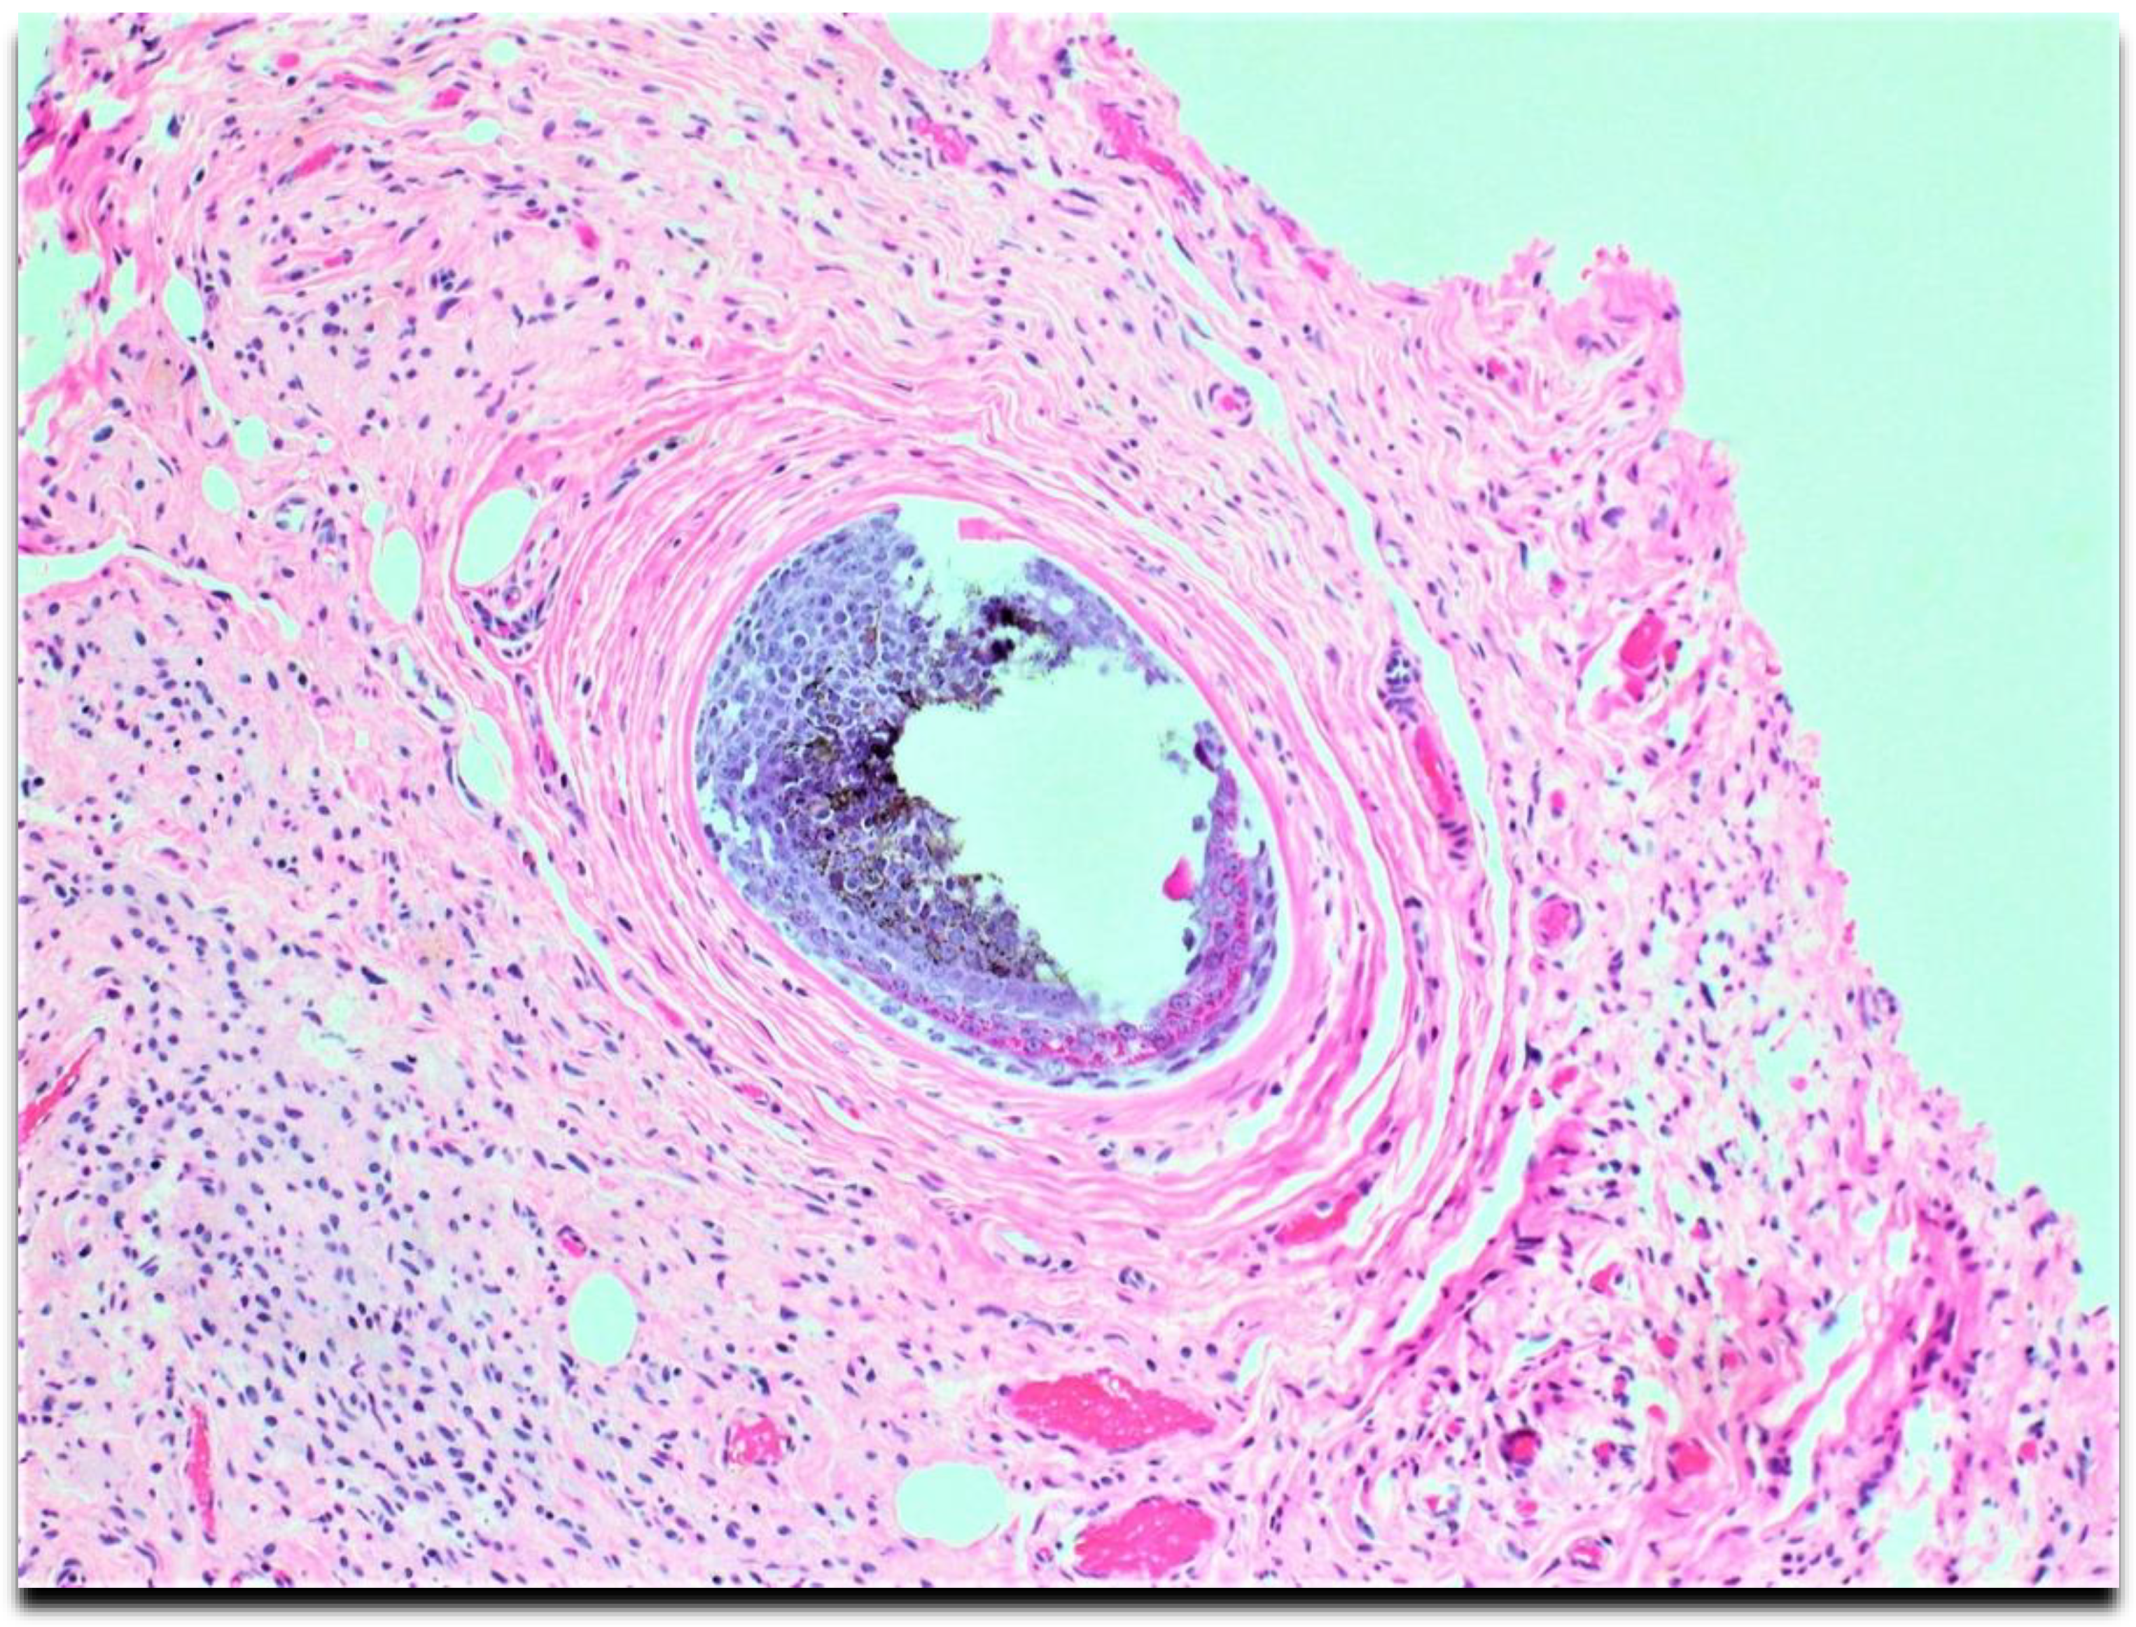

Microscopically, the lesion diffusely involved the skin dermis and subcutaneous soft tissue. Numerous vascularized areas were interspersed throughout the lesion, consistent with surgical findings. Loosely arranged spindle cells with hyperchromatic nuclei were arranged irregularly within the background of the collagenous stroma. Spindle cells had prominent infiltration of adipose tissue (Figure 1 and Figure 2) with the proliferation and entrapping of cutaneous adnexa structures (Figure 3).

Plexiform neurofibromas have varying presentations depending on the extension depth and location site. They arise from deeply located spinal nerve roots and have a highly ill-defined hyperpigmented and torturous appearance. Common symptoms include pain, numbness, and mass effect. Similar to diffuse neurofibroma, they can grow immensely, often surrounding multiple nerve fascicles [1,4]. The subtype is found in approximately 30-40 % of patients with NF1 and is considered pathognomonic for the hereditary disorder [1,4]. Diffuse neurofibroma is differentiated from plexiform neurofibroma subtypes by its defining characteristic of dermal and subcutaneous proliferation that irregularly entraps adnexa structures (Figure 3) and invades underlying adipose tissue (Figure 1 and Figure 2). Pseudomeissenerian bodies (Wagner-Meissner bodies), composed of eosinophilic fibrillary and whorled Schwann cells, are a unique characteristic feature of diffuse neurofibroma [1,10]. S100 is a sensitive but nonspecific marker for Schwann cells in neurofibromas (Figure 4). In diffuse neurofibromas, CD34 staining is fingerprint-like (Figure 5) because it stains admixed spindled fibroblasts in between collagen bundles [1]. Plexiform neurofibroma can be differentiated from diffuse neurofibroma due to its serpentine growth pattern, possible atypia, and irregular hypertrophic nerve fascicles [1,4]. The patient’s clinical presentation of headache and tenderness is more in line with a plexiform neurofibroma. However, histopathological findings were consistent with a diffuse neurofibroma as microscopic examination did not reveal nuclear atypia or hypertrophic nerve fascicles. Additionally, she did not exhibit the usual alternative traits associated with NF1. The neurofibroma subtypes are microscopically similar because they comprise loosely arranged ovoid to spindle cells with hyperchromatic buckled to wavy nuclei within a background of myoxid to pale pink collagenous matrix [1,8,9].

Figure 3. High-power microscopic examinations show spindle cells' entrapment of adnexa structures.